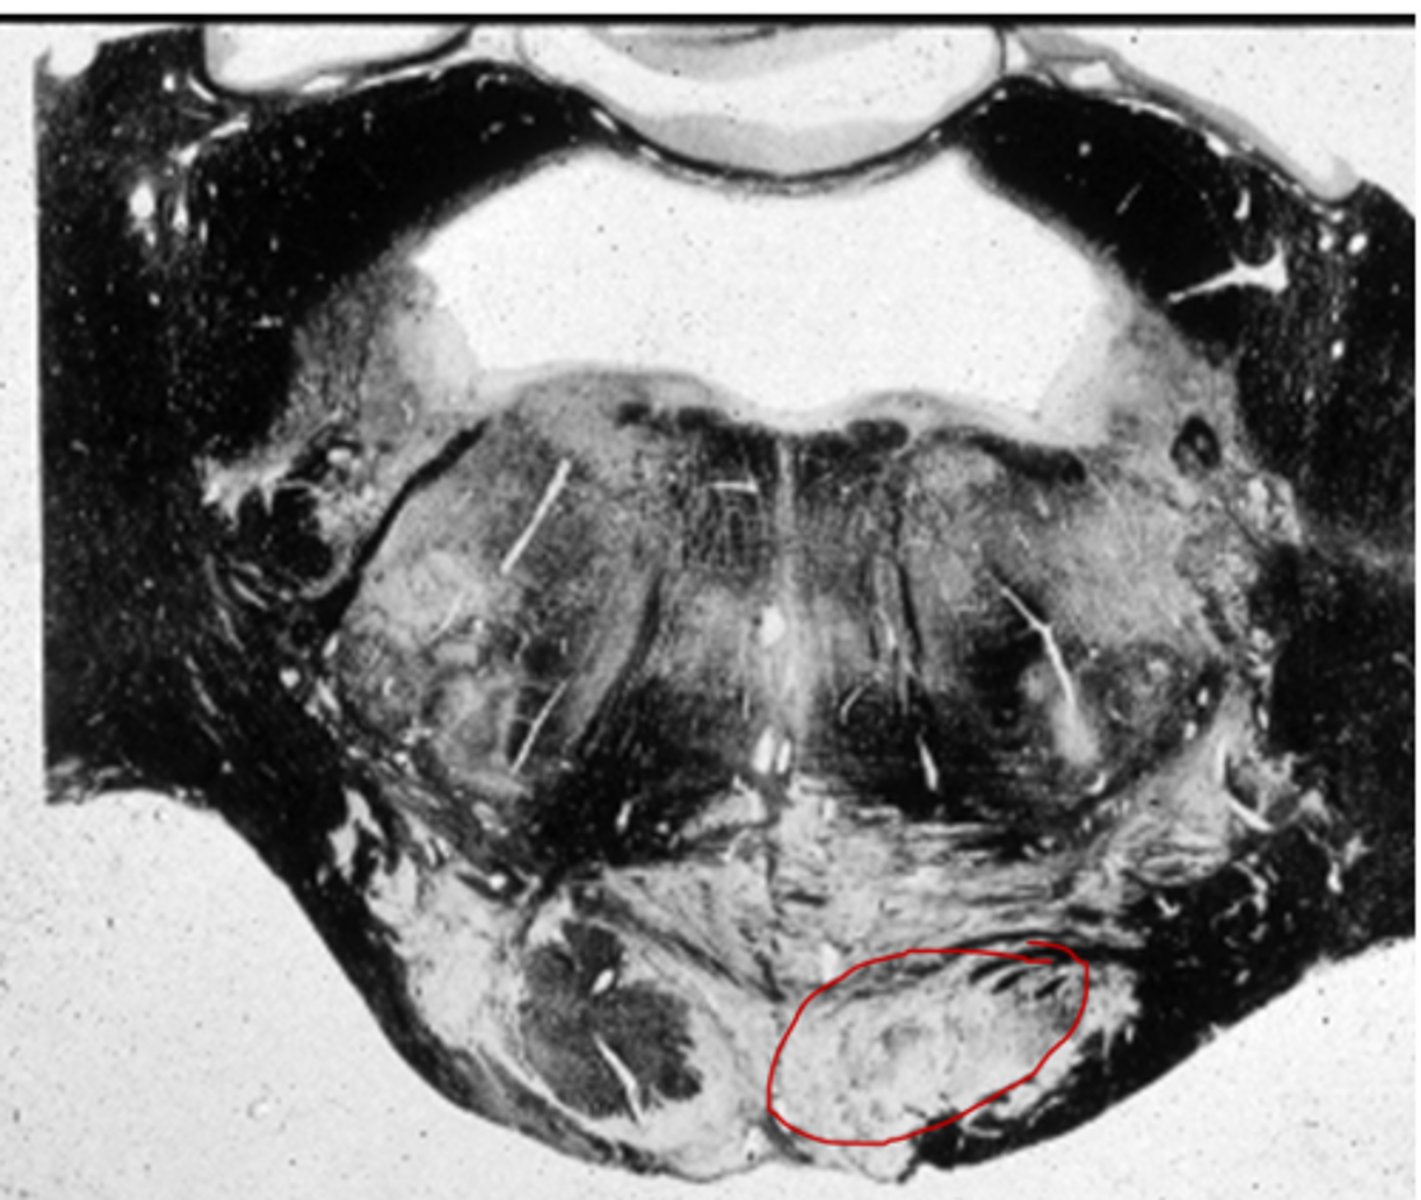

the 'olives'

oval-shaped structures located on the anterior surface of the medulla, lateral to the pyramids

inferior olivary nucleus

associated with motor coordination & fine-tuning of movements